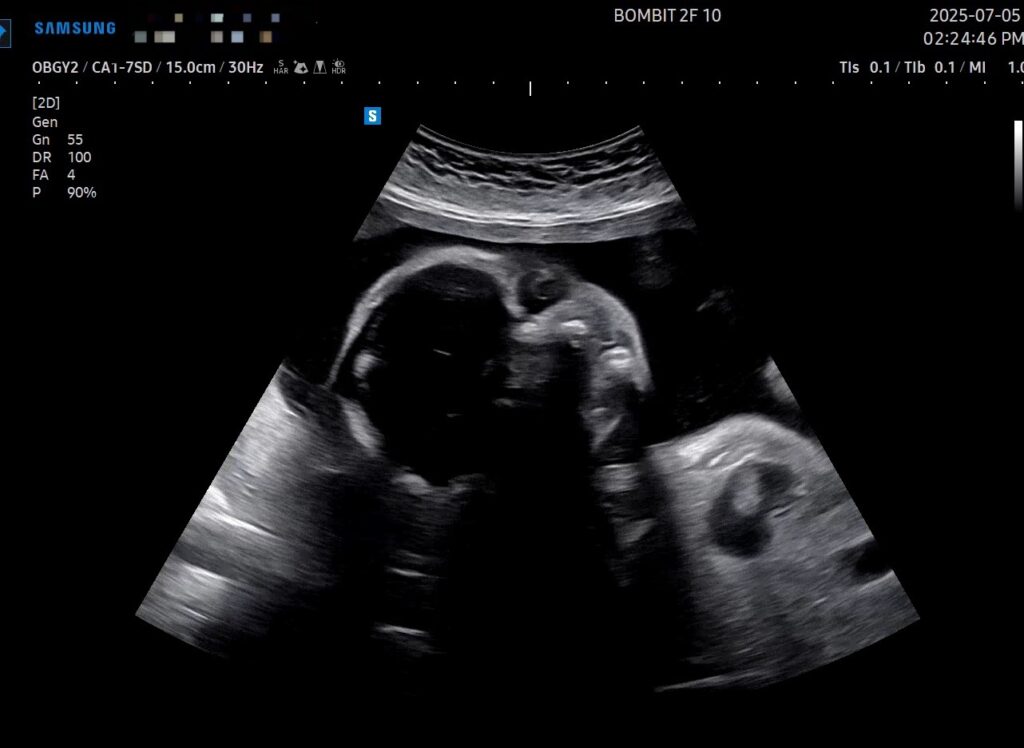

이건 초음파 사진!

초기 때는 초음파 옆모습 단면이 아기처럼 예쁘게 보였는데, 전반적인 크기가 커지면서 눈두덩이랑 턱뼈가 초음파로 적나라하게 드러나게 되었다. 그래서 초음파 사진이 약간 괴기스러워졌다..ㅋㅋㅋ